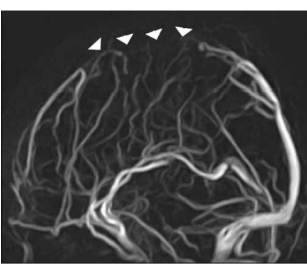

What radiological technique is used to image veins?

Venography

What is wrong with this patient?

The venography shows interrupted flow of the sagittal sinus - so they likely have a venous sinus thrombosis.

What are the symptoms of Cerebral Venous Sinus Thrombosis (CVST)?

Worsening headache

Seizures

Altered mental status

It may cause a stroke

Can lead to a coma

Is a CVST common?

No, they are very rare. If a patient has one, it is very likely they had one or more risk factors for it - like pregnancy, hormonal contraceptives, cancer etc.